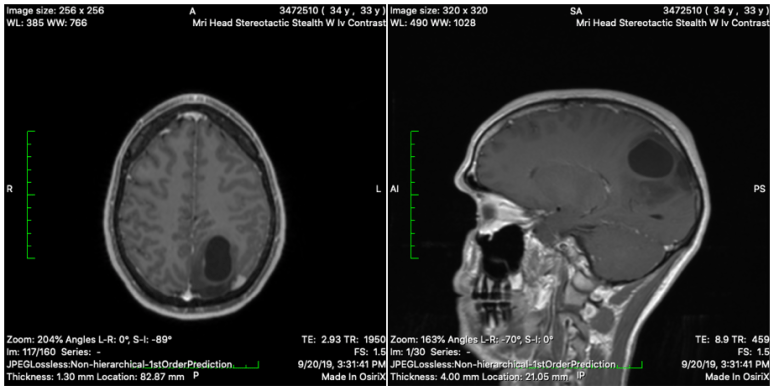

How can I possibly feel any of these things with my current situation? A few months ago, my husband had surgery to remove a tumor in his brain, and was diagnosed with brain cancer.